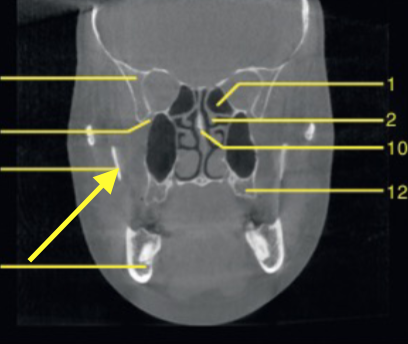

coronal

what plane is this slice

what plane

posterior of maxillary sinus

where is this slice

mandibular canal/inferior alveolar canal

what is the ARROW pointing to

orbital roof

what are the arrows pointing to

nasal floor

identify the structure indicated by the ARROW